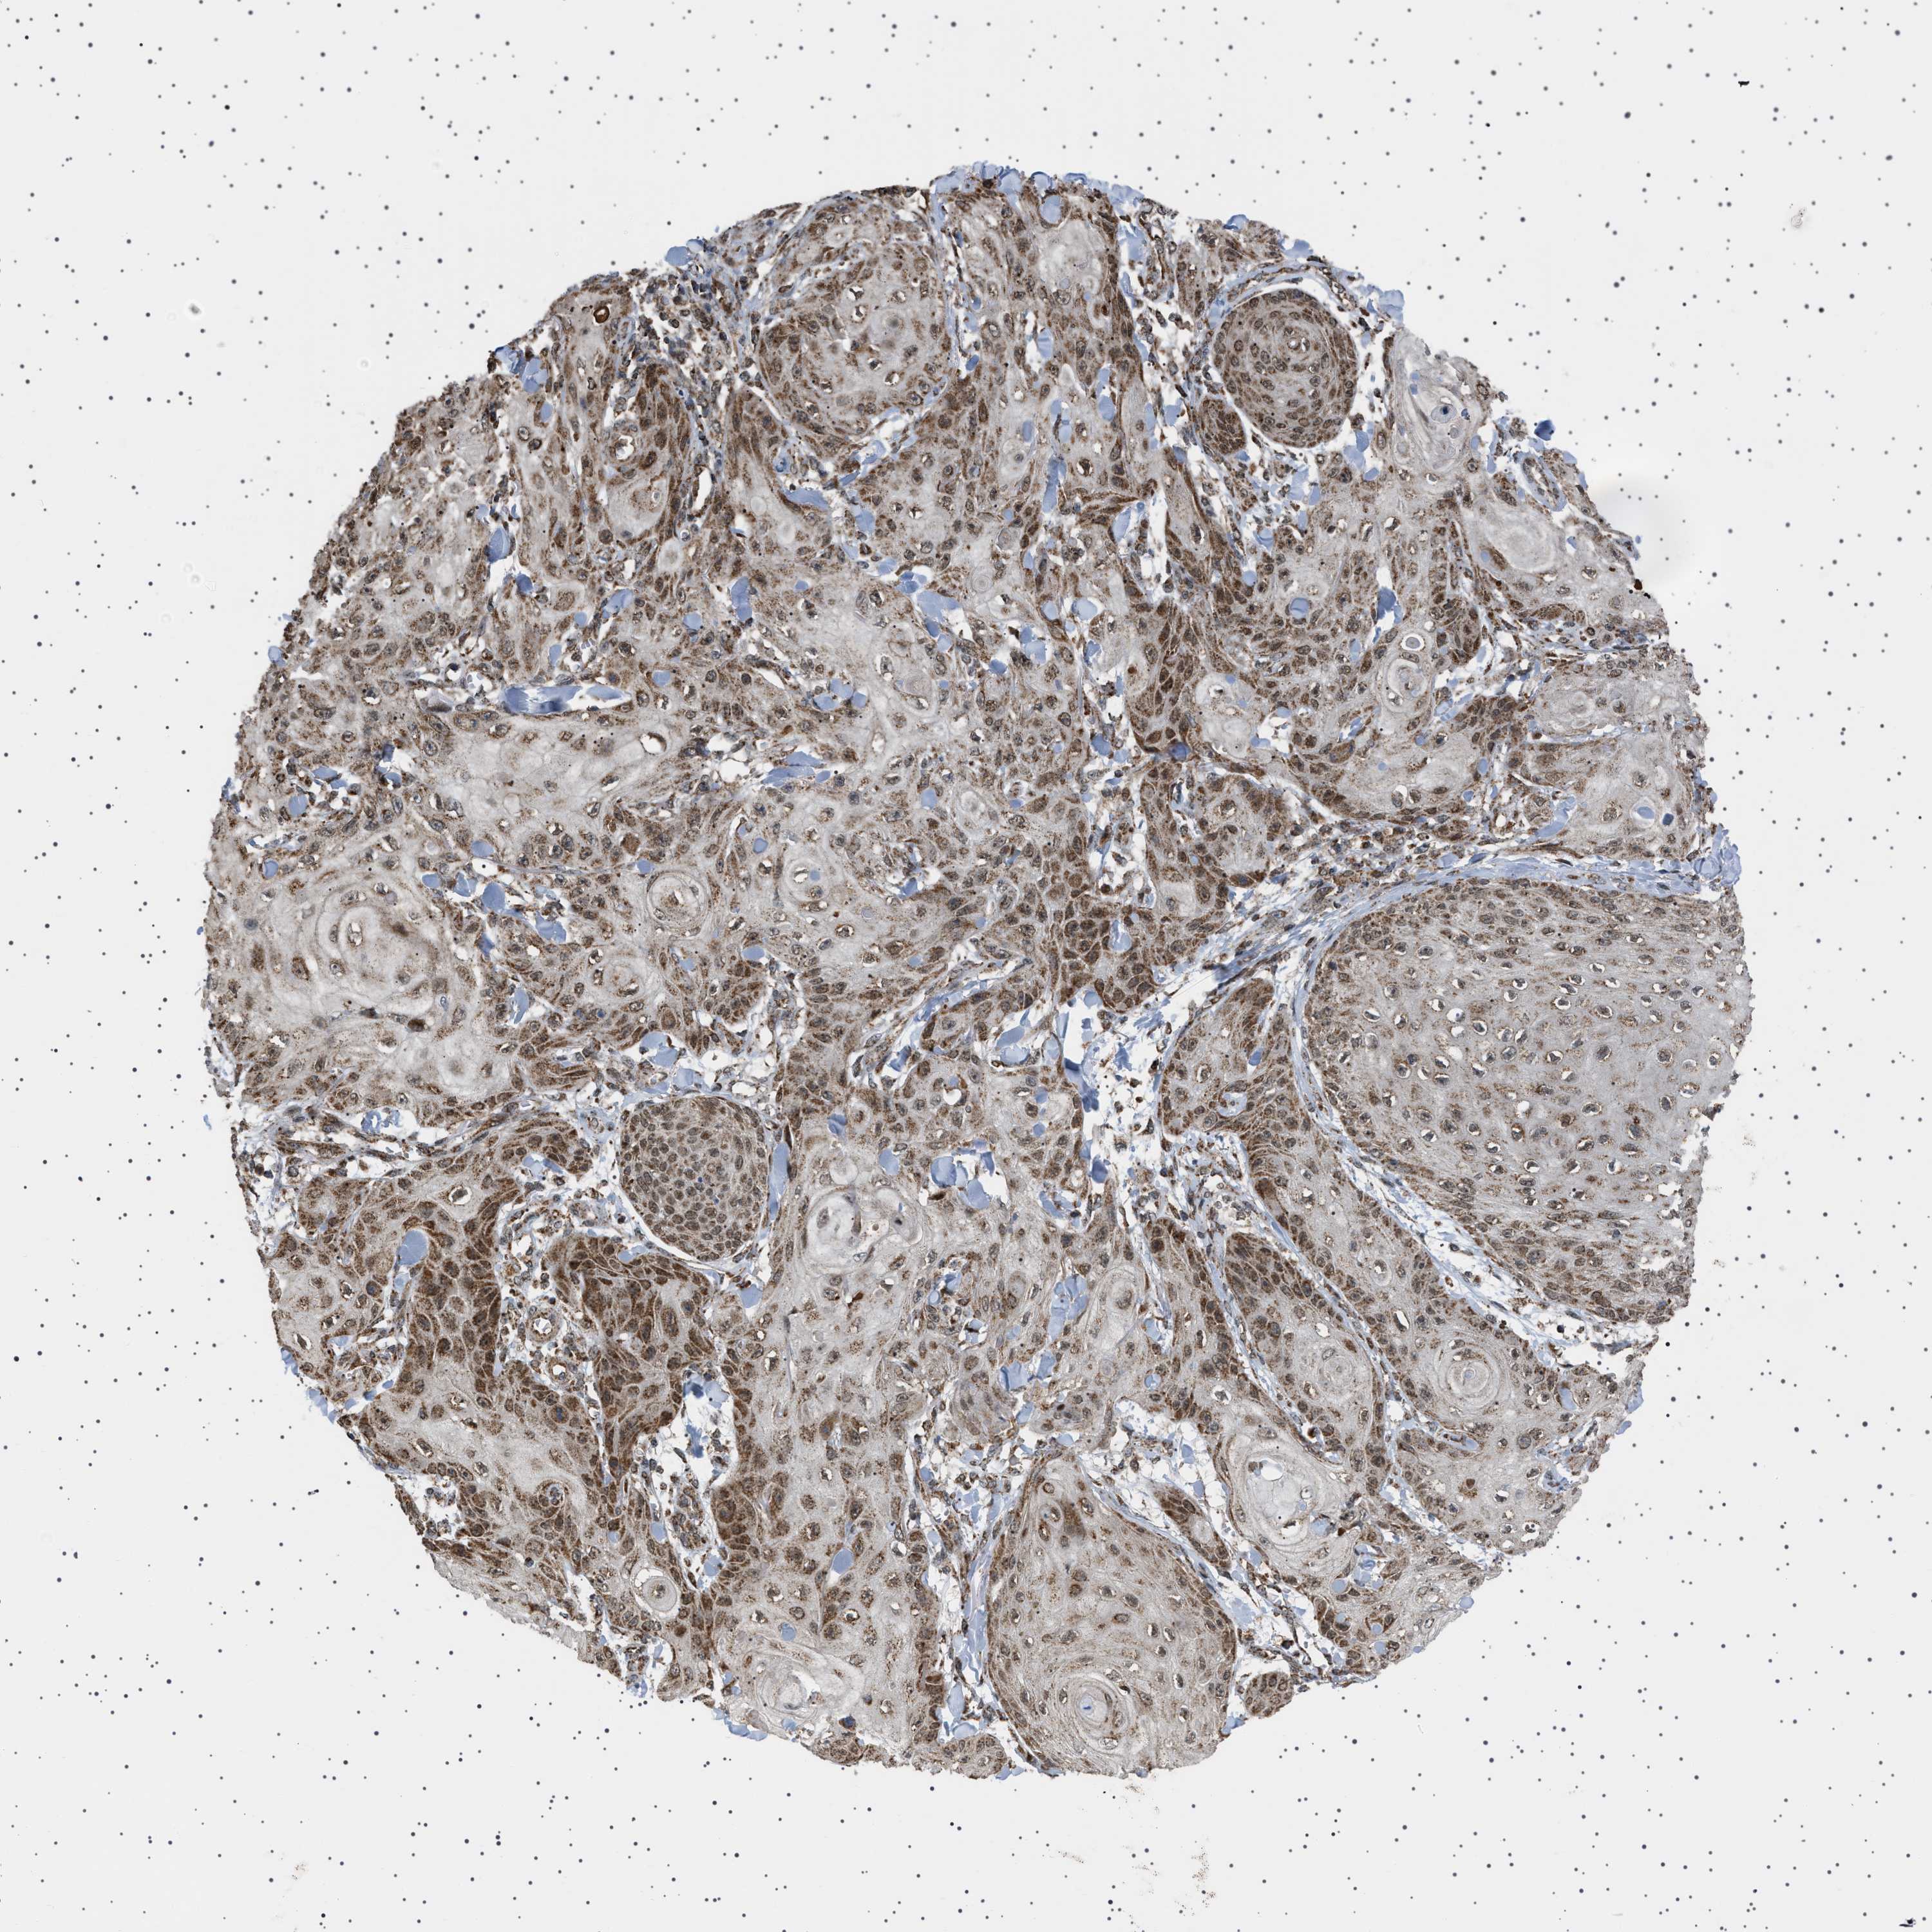

SKIN CANCER - Protein expressioni

A mouse-over function shows sample information and annotation data. Click on an image to view it in a full screen mode. Samples can be filtered based on level of antibody staining by selecting one or several of the following categories: high, medium, low and not detected. The assay and annotation is described here.

Each image is clickable and will lead to virtual microscopy that enables deeper exploration of all samples and also displays staining intensity scores, fraction scores and subcellular localization as well as patient and tissue information for each sample.

Antibody HPA017214

Staining

High

Intensity

Strong

Quantity

>75%

Location

Nuclear

Squamous cell carcinoma in situ, NOS